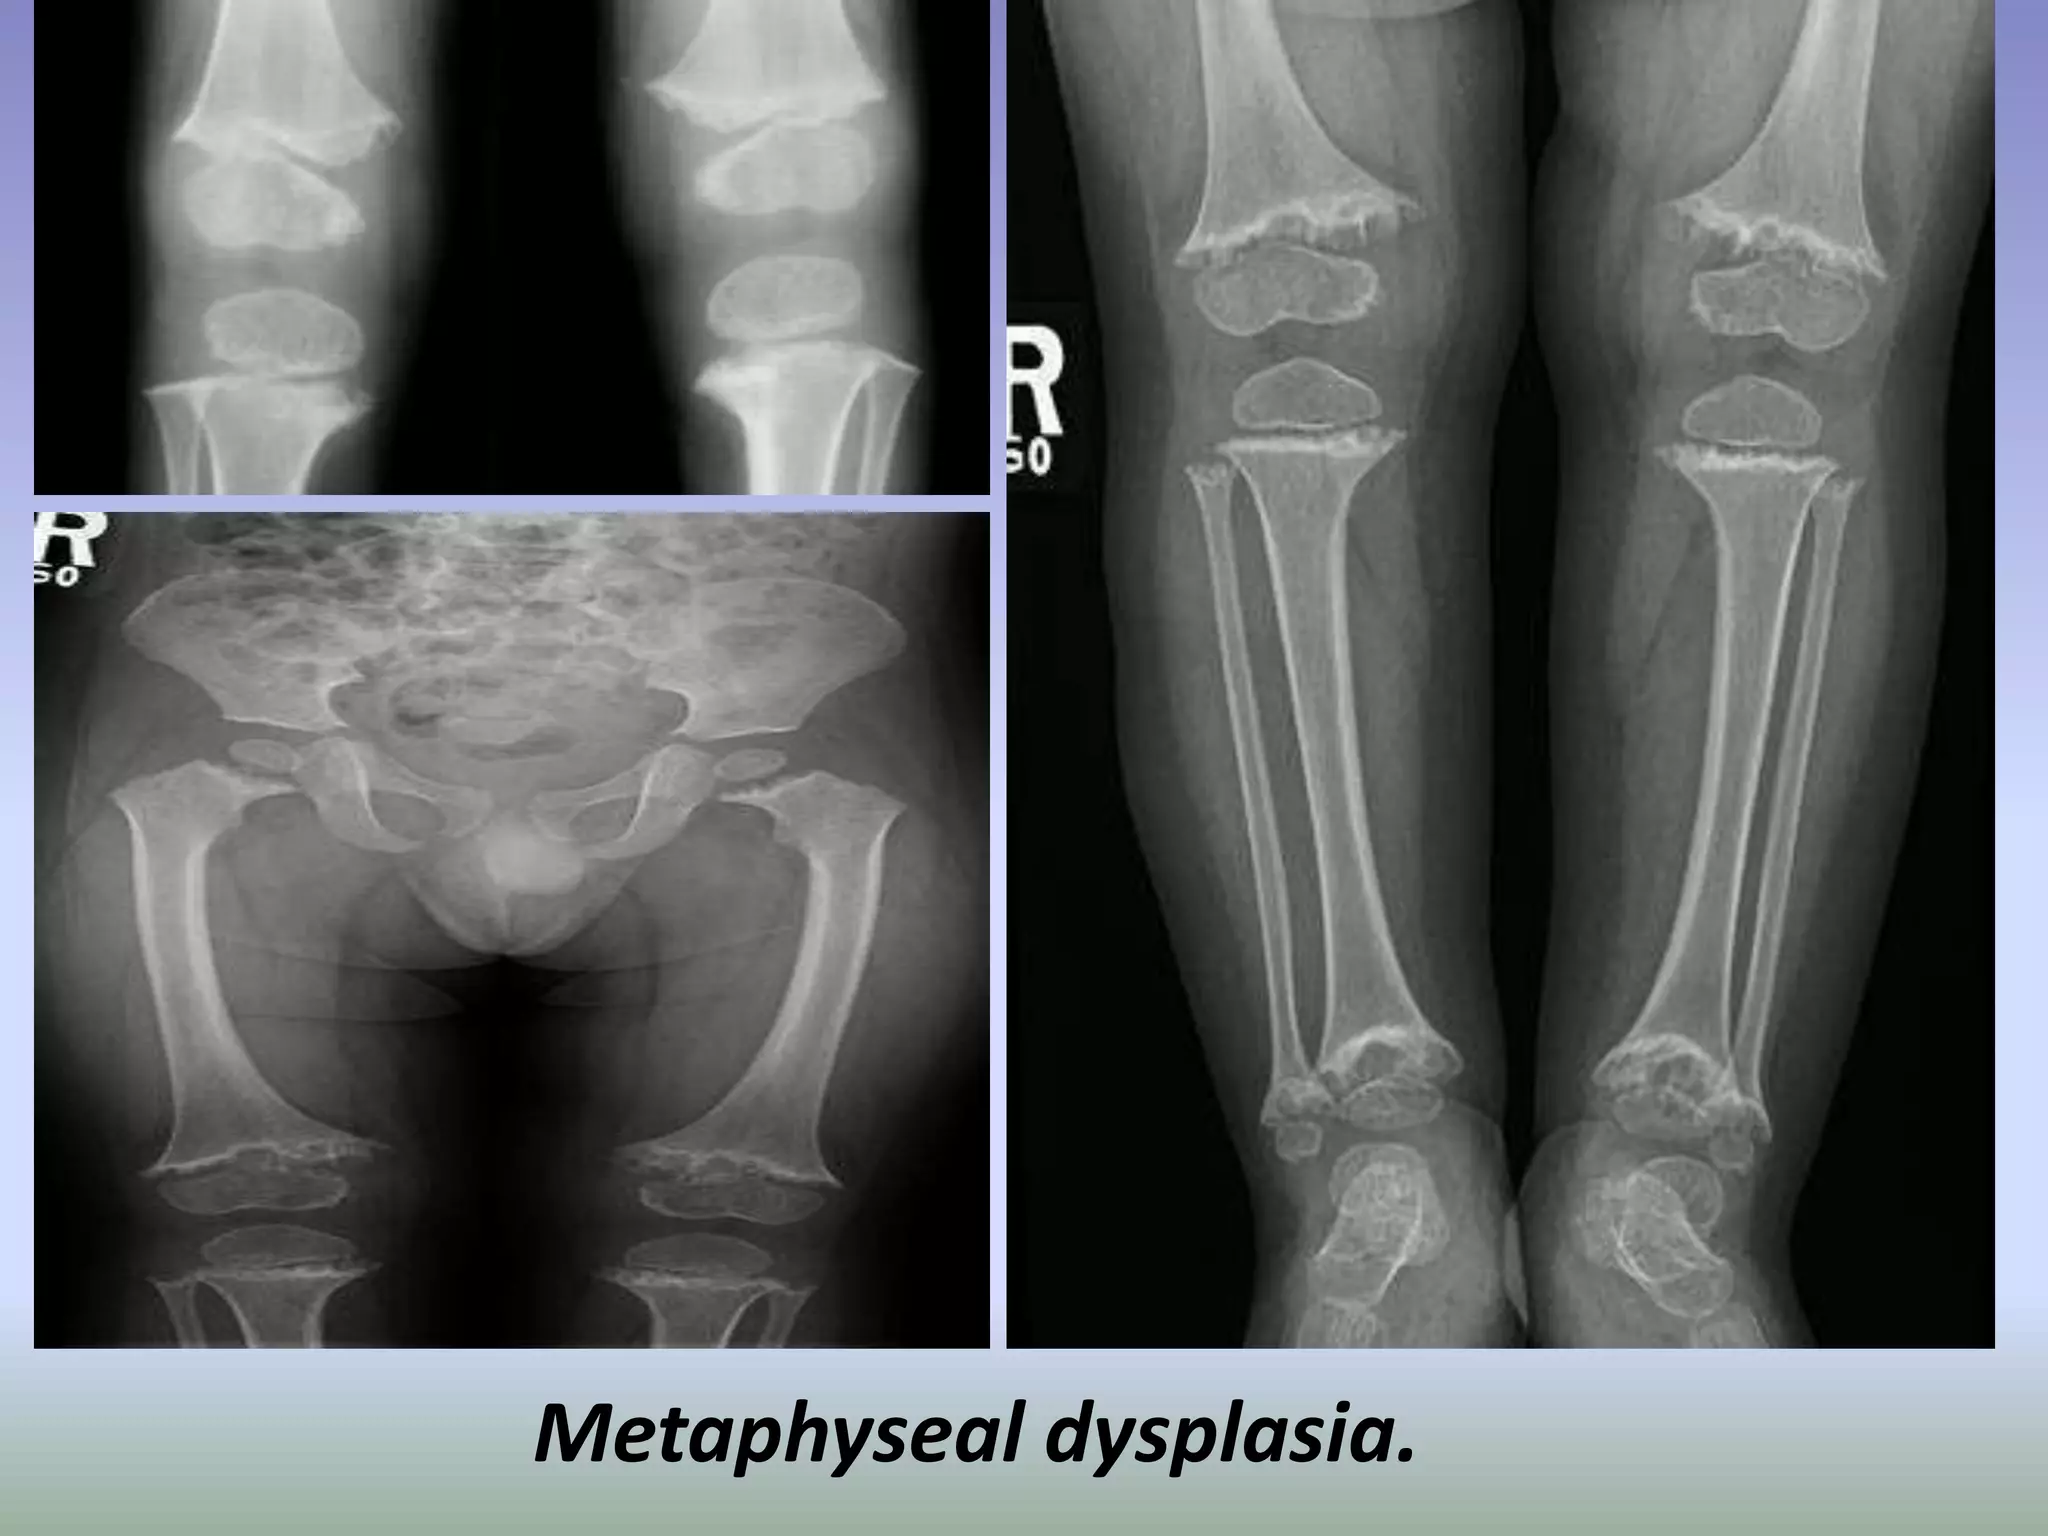

Metaphyseal dysplasia. Standing radiographs of the knees showing

Metaphyseal dysplasia.